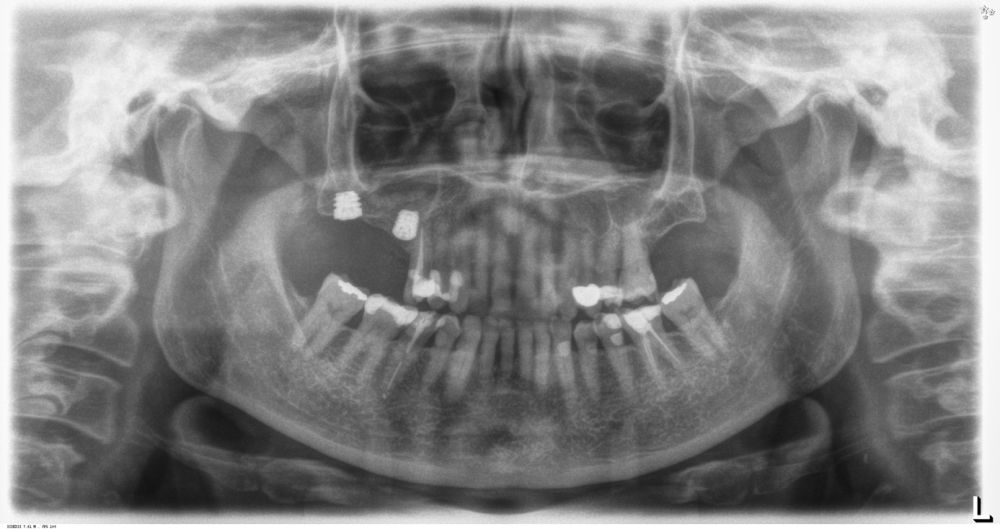

Introducción. El abordaje transcrestal del seno maxilar con y sin material de relleno como injerto es una técnica ampliamente extendida en nuestros días. Generalmente se combina con la utilización de implantes cortos y extracortos. En este trabajo, presentamos una serie de casos tratados con un protocolo unificado con un seguimiento de 10 años.

Material y método. Se ha llevado a cabo un estudio retrospectivo de pacientes tratados mediante implantes extracortos (5,5 y 6,5 mm de longitud) colocados mediante elevación transcrestal sin el uso de injerto. Como variables principales se han estudiado: la pérdida ósea crestal de los implantes y la ganancia en altura sobre el ápice. Como variable secundaria se ha estudiado la supervivencia de los implantes.

Resultados. Fueron reclutados 13 pacientes en los que se insertaron 30 implantes. Una vez insertados y cargados los implantes, la altura media final fue de 9,68 mm (+/- 2,66), lo que supone una ganancia promedio de 5 mm. A los 10 años, se observó una disminución media de la altura ósea ganada en los implantes en conjunto de 0, 29 mm (+/- 0,77). La media de la pérdida ósea mesial fue de 0,73 mm (+/- 0,75 mm) y la media de la pérdida ósea distal fue de 0,98 mm (+/- 1,2 mm). La supervivencia fue del 100%.

Los senos tratados con la técnica de elevación transcrestal sin material de relleno muestran un incremento de entre 2,5 mm12,13 hasta 4.4 mm14,15 en la altura ósea lograda sobre el ápice y una supervivencia de los implantes que se sitúa entre un 94 y un 100%16-17. En este trabajo se presenta un estudio retrospectivo donde se ha evaluado la inserción de implantes extracortos (5,5 y 6,5 mm) en zonas posteriores maxilares mediante la técnica de elevación de seno transcrestal con la fresa de ataque frontal sin la utilización de material de injerto, con un tiempo de seguimiento de 10 años para poder objetivar el comportamiento de los implantes a largo plazo y de la técnica empleada.